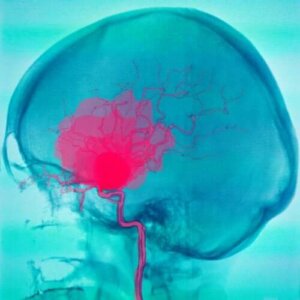

Субарахноїдальні та субдуральні крововиливи

При субарахноїдальних та субдуральних крововиливах спочатку витікає кров із судин. Ці судини знаходяться в просторі між оболонами, тому це пошкоджує тканини мозку.

Субарахноїдальні крововиливи

Субарахноїдальні крововиливи трапляються, коли між павутинною і м’якою оболонами є скупчення крові. Кров зазвичай надходить з артерій. Це може мати безліч різних причин. Найбільш поширеним є розрив аневризми. Однак вони можуть мати й інші причини.